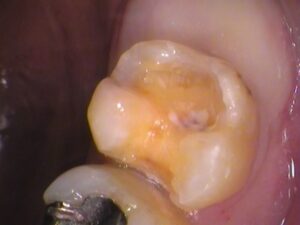

また、

セメントが入っていた内部にも虫歯が広がっていました。

隙間から入り込まれたのか、

以前の虫歯の取り残しなのか、

はっきりとは分かりませんが、虫歯は取り除きましょう。

染色を繰り返しながら、

虫歯を丁寧に取っていきます。

虫歯を全部とると、

このような状態です。

検知液で染まらないところまできました。

内部は健康な黄色い象牙質が見えています。

歯の神経までは達しませんでしたので、

神経の治療はしなくて済みました。